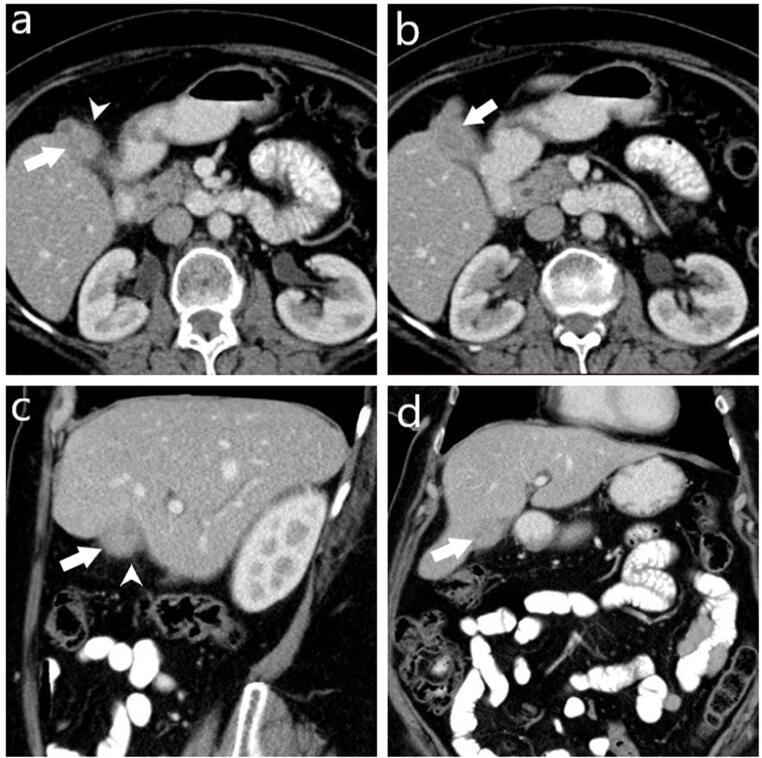

Background: Xanthogranulomatous cholecystitis (XGC) is a rare, chronic gallbladder inflammation often mistaken for gallbladder cancer (GBC) on imaging. Accurate differentiation is vital for appropriate treatment. This study aims to enhance computed tomography (CT) scan diagnostic accuracy for distinguishing XGC from GBC.

Methods: This retrospective study included patients diagnosed with XGC and GBC between 2014 and 2023. CT images of 70 patients (16 GBC, 54 XGC) were reviewed. Radiologists assessed CT parameters: gallbladder wall thickening, intramural hypoattenuating nodules, enhancement characteristics, mucosal line continuity, pericholecystic fat stranding, presence of stones, bile duct dilatation, hepatic invasion, invasion to adjacent structures, and lymph node size.

Results: Among 70 patients, there were 38 males (54%) and 32 females (46%), with a median age of 62 years. GBC patients were significantly older (median age 72 years) compared to XGC patients (60 years) (P=0.001). Diffuse gallbladder wall thickening was more frequent in XGC (70%) than GBC (12.5%) (P<0.001). Continuous mucosal lines and intramural hypoattenuating nodules were more common in XGC (P<0.001 and P=0.010, respectively). Intrahepatic bile duct dilatation and invasion to adjacent structures were significantly linked with GBC (P<0.001 and P=0.043). Lymph nodes with a short axis>8 mm indicated GBC (P<0.001), with a cutoff providing 71.4% sensitivity and 84% specificity (AUC: 0.843, P<0.001). CT showed 75% sensitivity (95% CI: 48-93%), 74% specificity (95% CI: 60%-85%), and 74% accuracy (95% CI: 62%-84%).

Conclusion: CT imaging can effectively differentiate XGC from GBC, and larger studies can further improve diagnostic accuracy.